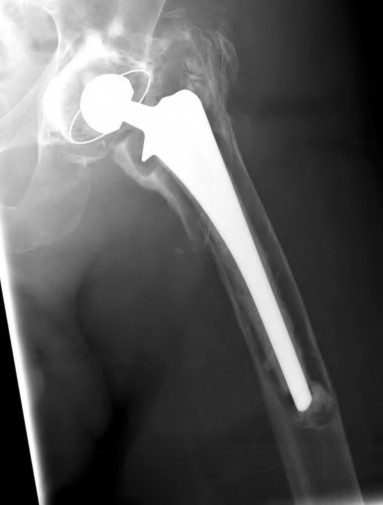

A 72-year-old female falls and sustains a periprosthetic femur fracture around her cementless total hip arthroplasty. Radiographs reveal a fracture extending just distal to the tip of the stem. The stem is radiographically loose, but there is excellent proximal and distal bone stock. According to the Vancouver classification, what is the fracture type and the recommended surgical treatment?

Explanation

Question 23

A 75-year-old female sustains a fall 5 years after a cementless THA. Radiographs show a periprosthetic femur fracture occurring around the stem tip. Intraoperative assessment reveals the stem remains firmly fixed in the metaphysis, and the proximal bone stock is adequate. According to the Vancouver classification, what is the fracture type and the standard recommended treatment?